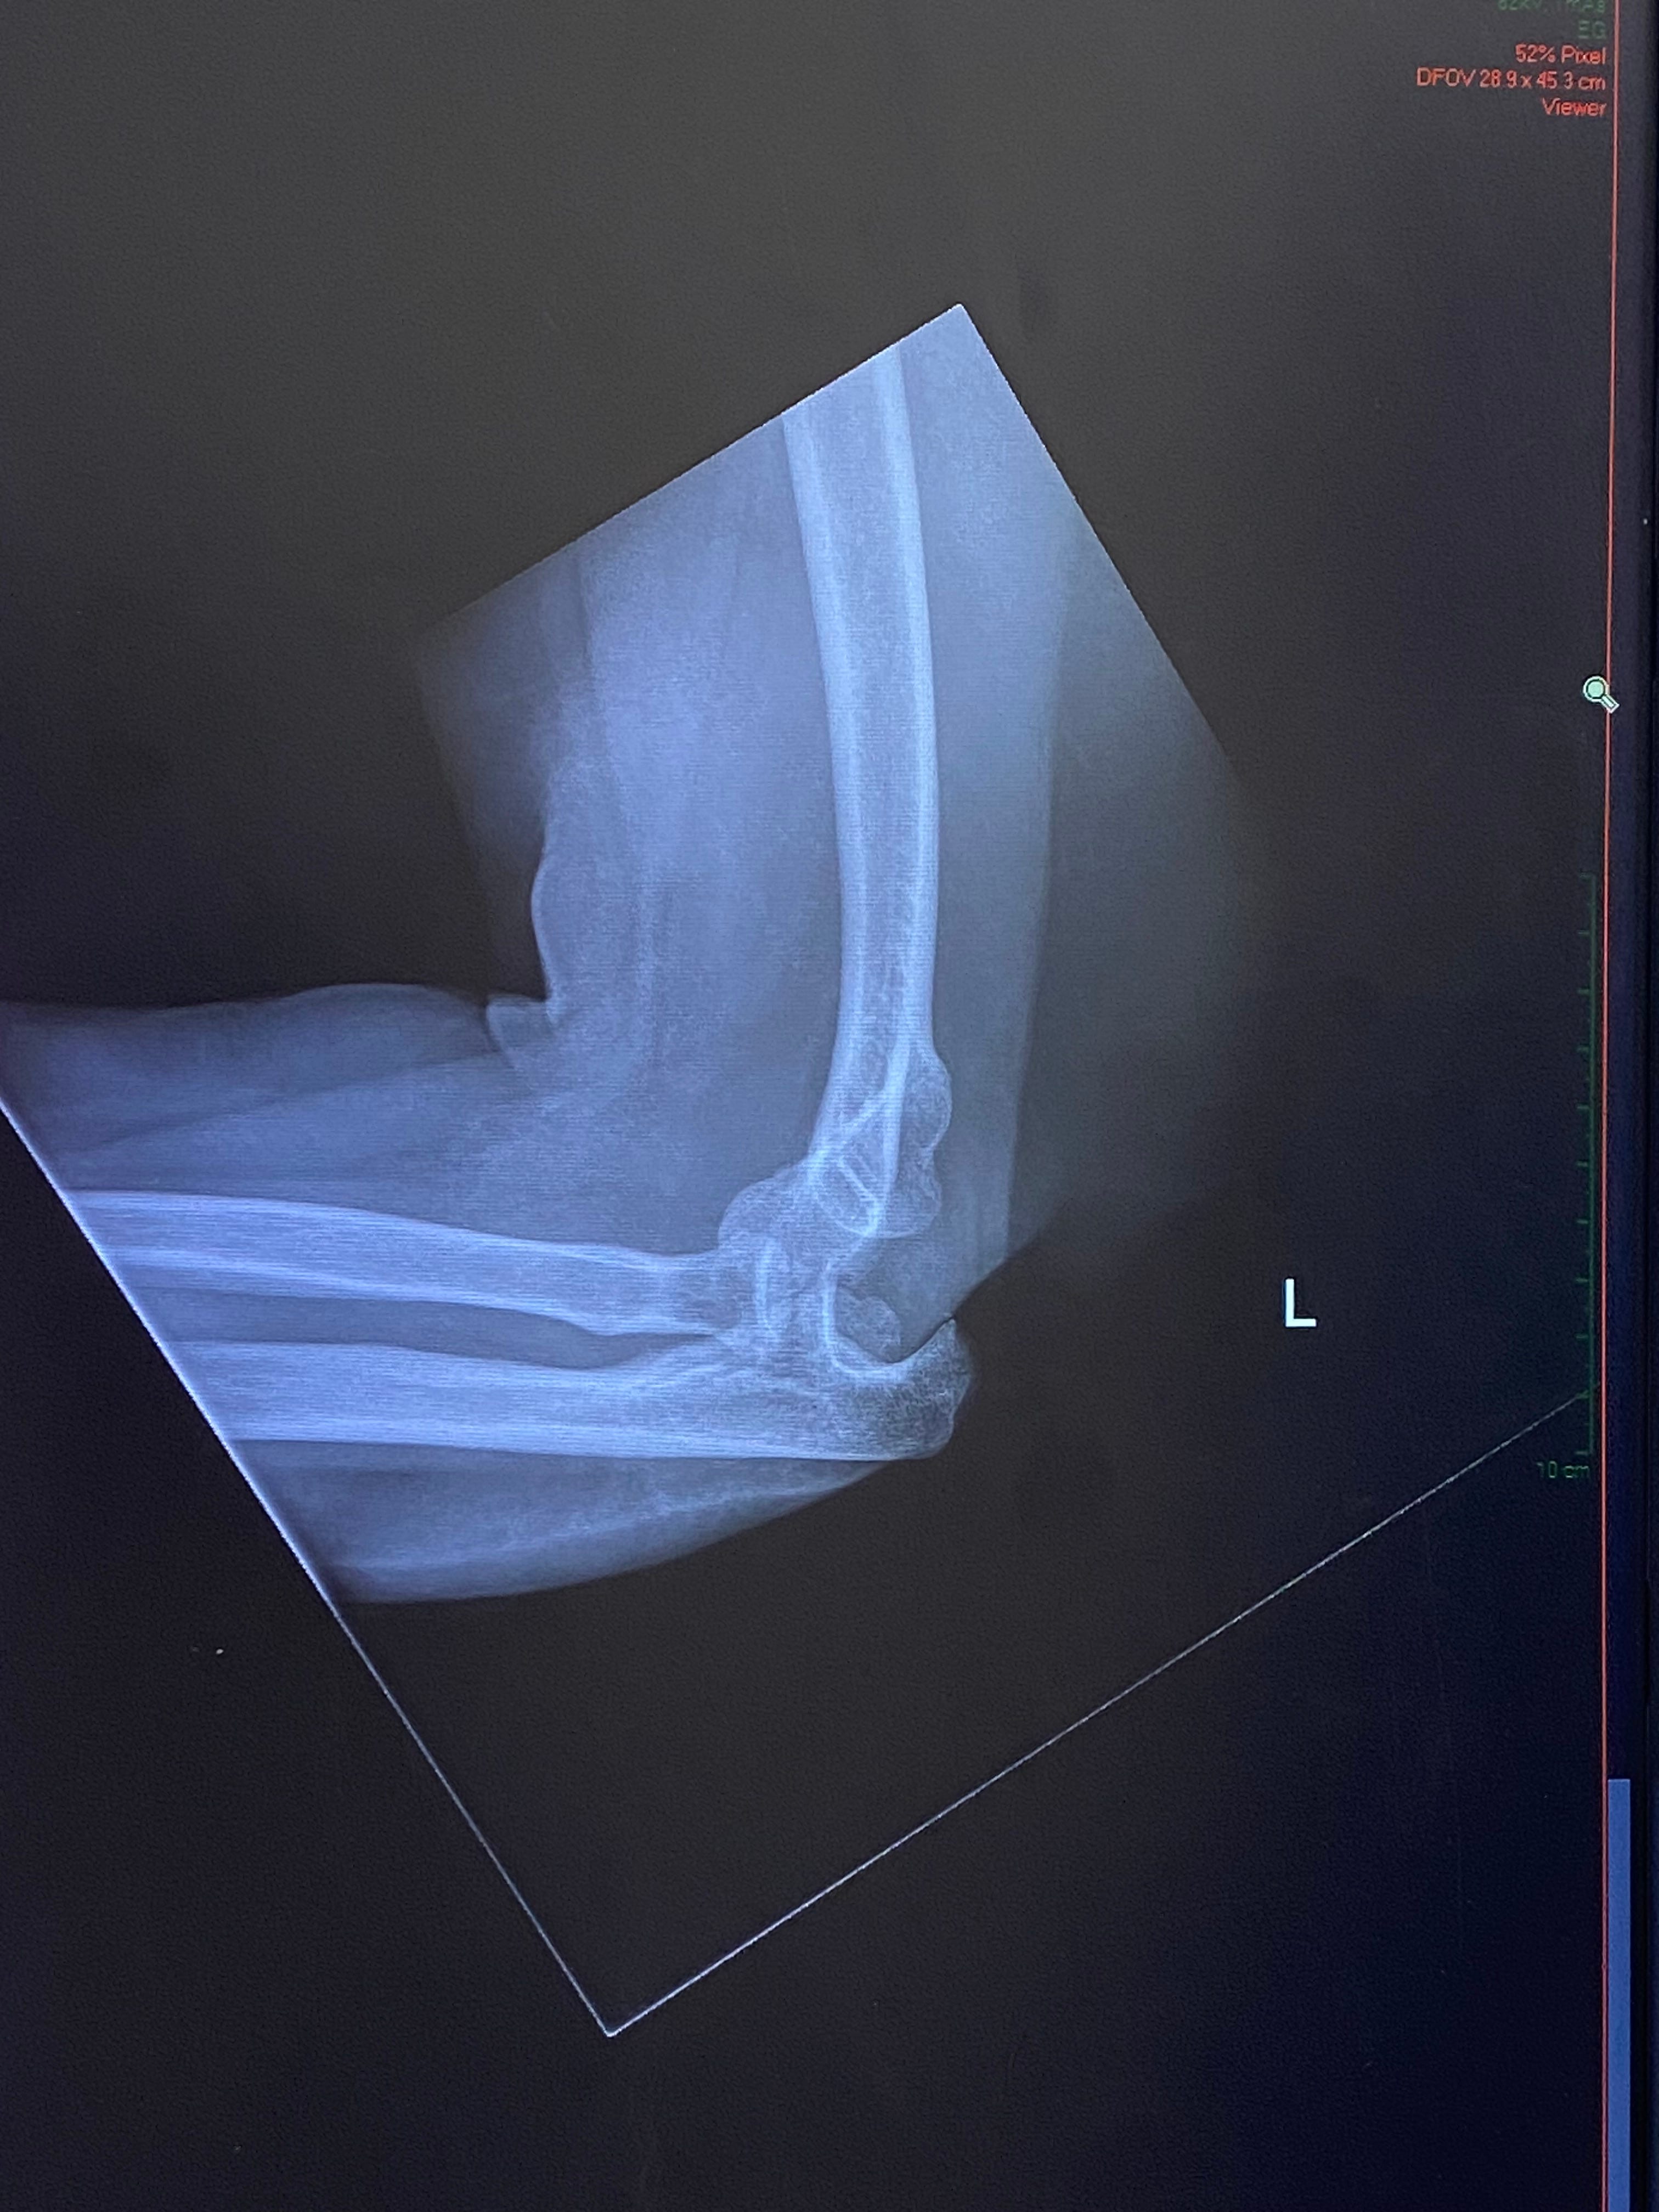

And then, as if breaking my arm (see above image) was 2025’s last laugh, things started to turn around. After winning my court case, the defendants appealed, leaving me lost in litigation and deeply depressed. A last-minute call to the Pro Bono Legal Hotline looking for advice miraculously landed me a legal team willing to take my case and handle the appeal hook line and sinker, for free!

My arm is still sore, after a month in a cast and another month in a very restrictive brace. But the trauma is fading, my elbow has stabilized and is healing quickly. I’m optimistic that a few more physio sessions and disciplined exercising will bring it back to fully functional before the winter is out.